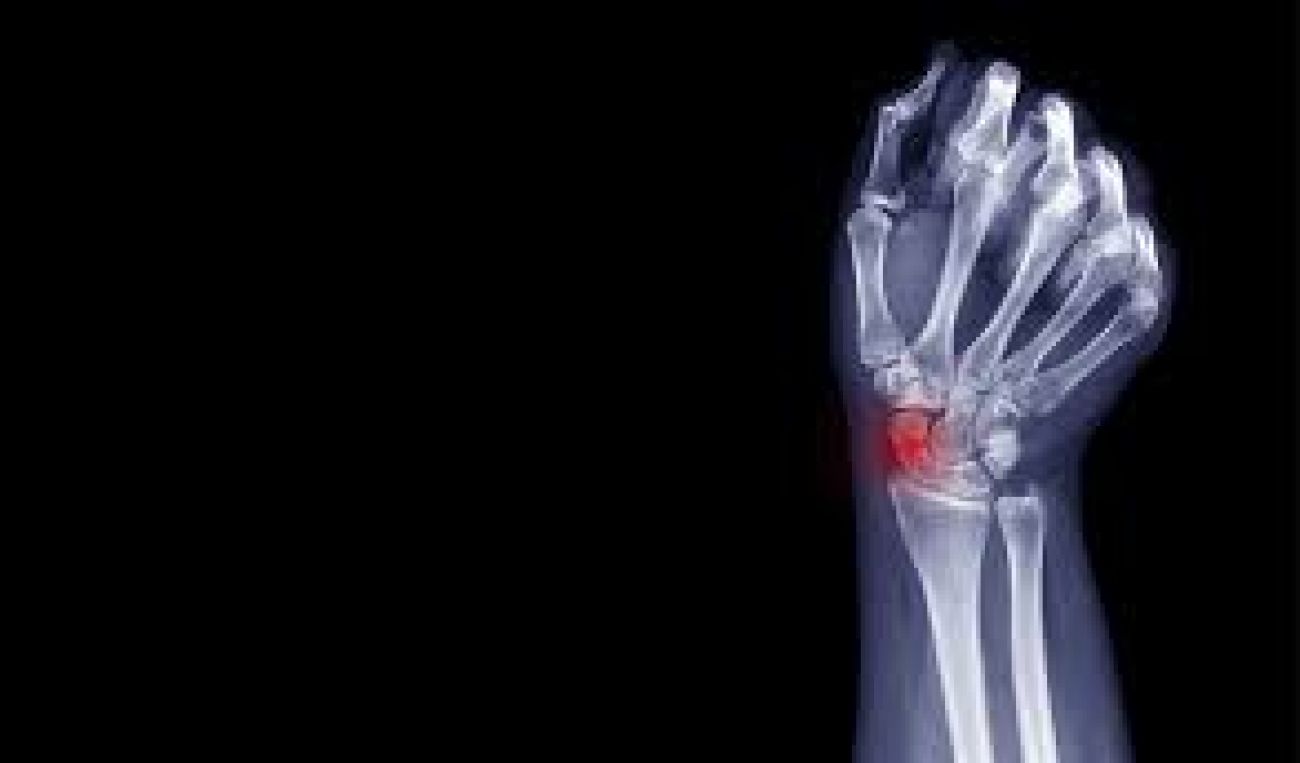

Fratura do escafoide

A Fratura do Escafoide é a quebra de um dos oito pequenos ossos do carpo (punho). O escafoide é o osso mais frequentemente fraturado no carpo.

Este osso tem uma importância particular porque a sua forma e posição são cruciais para a estabilidade e o movimento normal do punho. Além disso, o seu suprimento sanguíneo é precário e entra apenas por uma extremidade. Por isso, as fraturas do escafoide, especialmente as do polo proximal (a extremidade mais próxima do antebraço), têm um elevado risco de atraso na consolidação (união) ou de necrose avascular (morte óssea devido à falta de suprimento sanguíneo), o que torna o seu diagnóstico e tratamento urgentes.

• Radiografias (RX): São o primeiro exame. Devem ser tiradas múltiplas projeções, incluindo as projeções específicas para o escafoide. O problema é que as fraturas não deslocadas ou ocultas podem não ser visíveis nas radiografias iniciais (nas primeiras 2 semanas).